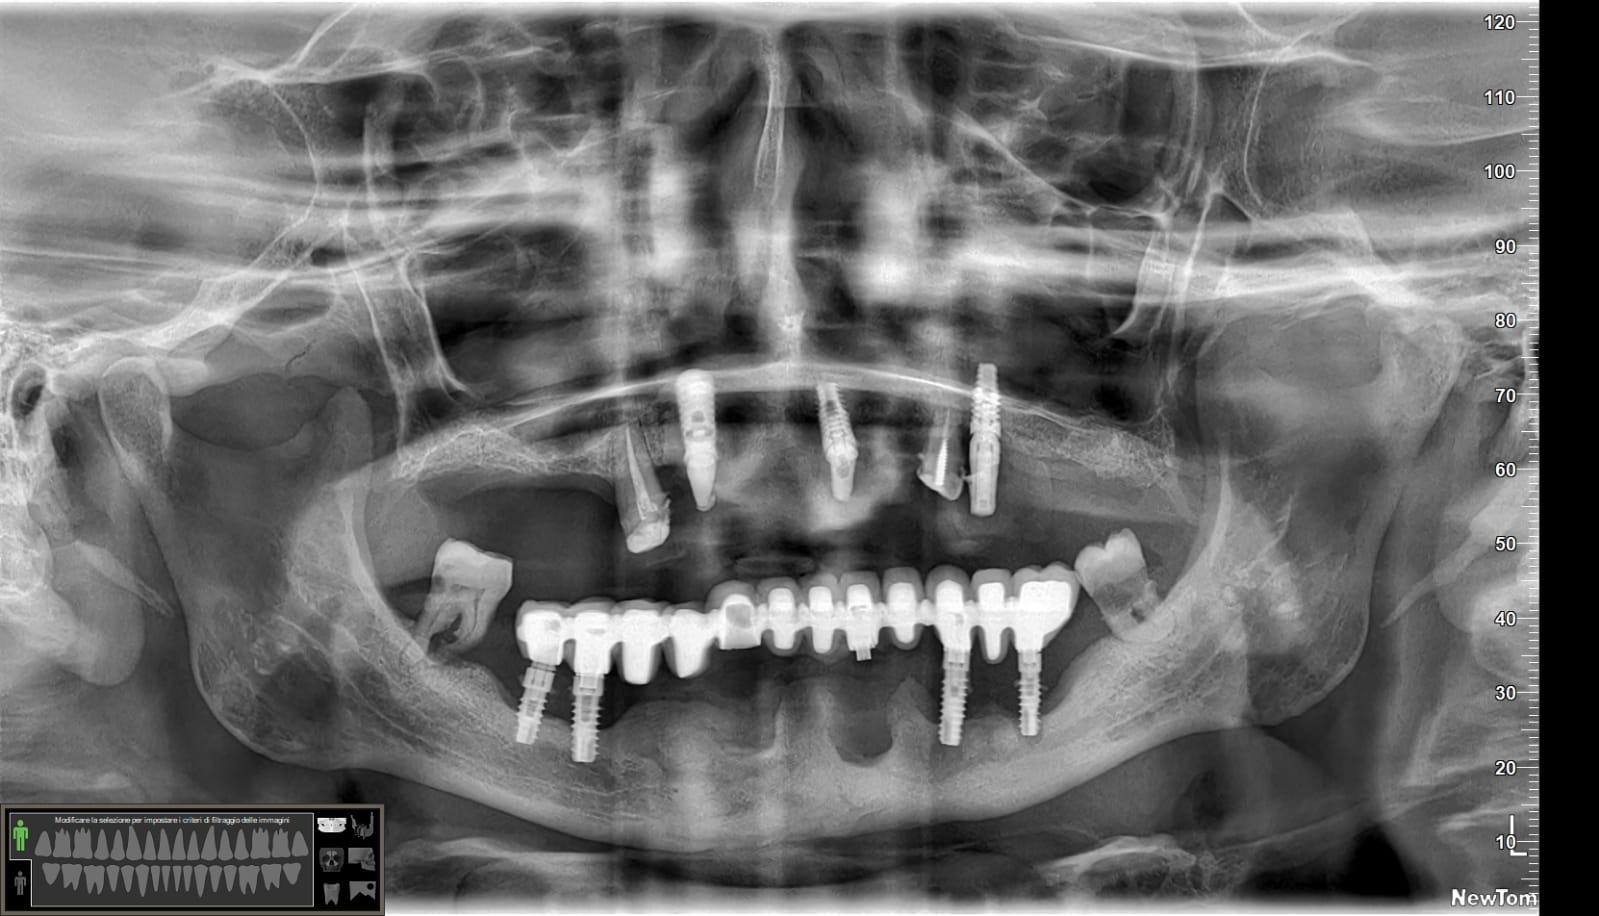

Effettivamente ci sono impianti vecchi da rimuovere e l’osso è scarso.

Nel caso di oggi vedremo il posizionamento di un impianto transinusale in questo paziente:

Ah… questa è la panoramica finale, inferiormente non ho trovato il modo per mettere 4 impianti ma solo tre… vedremo se aggiungerne uno. E non farti ingannare dall’immagine: il mentoniero di destra non è quello che sembra più distale ma quello meno visibile più mesiale.